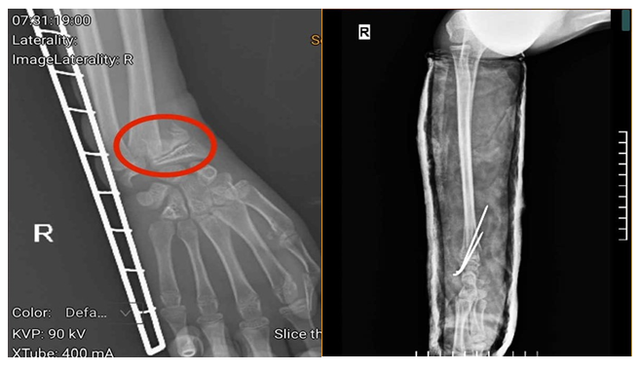

Tại Khoa Ngoại Chấn thương và Y học Thể thao, Trung tâm Chấn thương chỉnh hình, Bệnh viện Đa khoa tỉnh Phú Thọ, người bệnh được bác sĩ khám, chỉ định thực hiện các cận lâm sàng và được chẩn đoán gãy xương cẳng tay phải.

Tuy nhiên, do thời gian tổn thương kéo dài, người bệnh bị chấn thương trước khi vào viện 3 ngày, kèm theo việc gia đình cho người bệnh bó thuốc nam nên vùng xương và cơ bị tổn thương, có hiện tượng co cứng, đặc biệt, vùng xương gãy gần với sụn, nếu không can thiệp kịp thời sẽ ảnh hưởng đến khả năng vận động sau này.

Người bệnh được chỉ định phẫu thuật kết hợp xương bằng kỹ thuật C-arm với đội ngũ bác sĩ tay nghề cao, giúp nâng cao khả năng phục hồi tối đa.